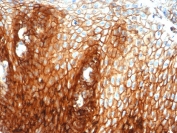

Recognizes a cell surface glycoprotein of 80-95kDa (CD44) on lymphocytes, monocytes, and granulocytes (Leucocyte Typing Workshop V). Its epitope is resistant to digestion by trypsin and chymotrypsin. This MAb selectively interferes with lymphocyte binding to lymph node, mucosal and synovial endothelium. The CD44 family of glycoproteins exists in a number of variant isoforms, the most common being the standard 85-95kDa or hematopoietic variant (CD44s). Higher molecular weight isoforms are described in epithelial cells (CD44v), which are believed to function in intercellular adhesion and stromal binding. CD44 immunostaining is commonly used for the discrimination of urothelial transitional cell carcinoma in-situ from non-neoplastic changes in the urothelium.